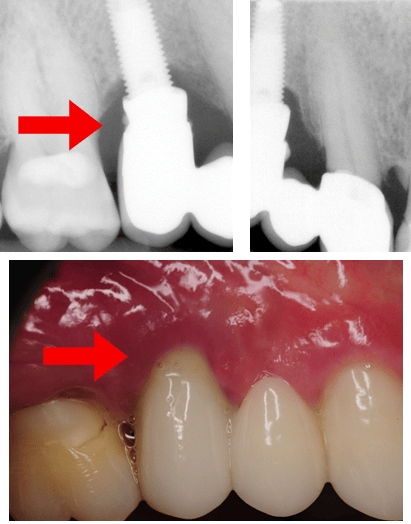

Case Example 2: A three-unit implant-tooth supported bridge

It is widely known that dental implants lack periodontal ligaments. This is one major characteristic that sets dental implants apart from teeth. Therefore, the concept of splinting a rigid ankylosed implant to a relatively mobile tooth remains controversial.

Some researchers believe “that the difference in support at both ends of the system places the implant at risk for complications.”5 This is a case example of a three-unit implant-supported bridge in place of teeth # 4-5 with obvious limitations for adequate hygiene attributable to design. When looking at the clinical image, the restoration may look appropriate, but the radiographs suggest otherwise.

Something else that needs consideration when examining dental implant restorations for hygiene accessibility is retention. This is a three-unit cement-retained implant tooth-supported bridge. Not only does the design of this bridge make hygiene challenging, but if you examine the radiograph closely, you will notice residual cement, which presents another risk factor for plaque accumulation and peri-implant disease.

Note radiographic residual cement and peri-implantitis with pus exudation.